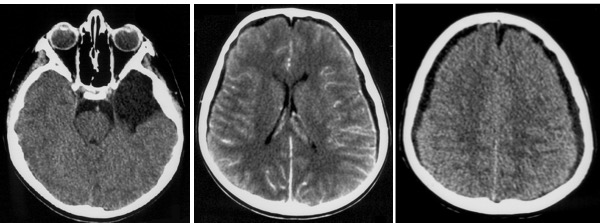

on retrouve une collection sous-durale hypodense, qui n’exerce pas d’effet de masse sur la ligne médiane si elle est bilatérale (Cf. ci-dessus), amis il existe un effacement des sillons et des citernes.

l’imagerie peut être trompeuse, l’HSD étant souvent isodense au cerveau et pouvant masquer totalement le kyste ; ce dernier n’est parfois visible qu’après évacuation de l’HSD, on en étudiant attentivement le scanner en coupes osseuses : on retrouve alors un scalopping de la grande aile du sphénoïde (Cf. ci-dessous)